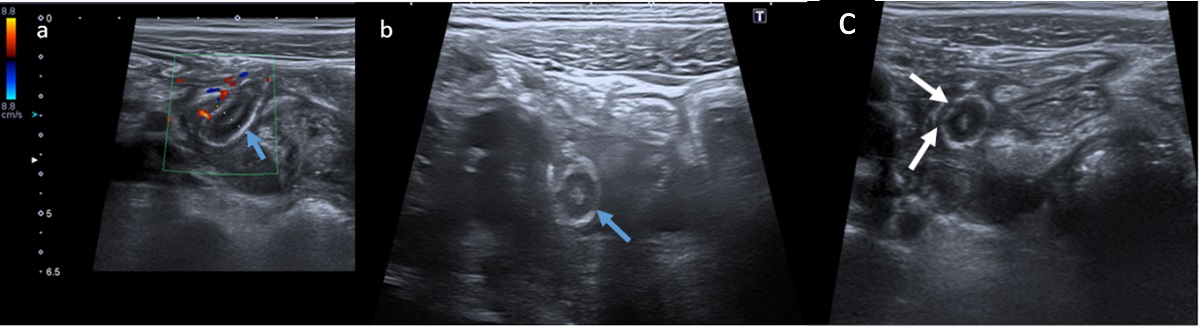

| Hallazgos ecográficos compatibles con apendicitis del muñón complicada: (a y b) estructura tubular con ecoestructura en capas compatible con muñón apendicular en planos axial y longitudinal (flechas azules). Presenta aumento de calibre (10 mm), engrosamiento de la capa submucosa (hiperecogénica), e hiperemia parietal vista en (a) como aumento de la señal Doppler; (c) discontinuidades en la capa submucosa compatibles con microperforaciones (flechas blancas) |

|---|